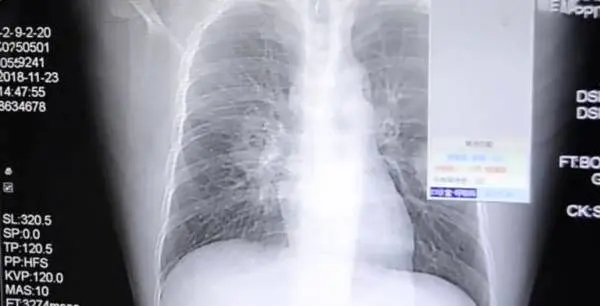

به گزارش منیبان؛ بوی جوراب !!! مگر می شود کسی تمایل به بو کردن جوراب هایش آن هم بعد از یک روز سخت کاری داشته باشد ؟ بله از قرار معلوم هستند افرادی که نه تنها جرات بو کردن جورابهایشان را دارند بلکه از این کار لذت می برند که این لذت به قیمت تهدید جانشان تمام می شود مثل مرد جوان چینی که با بو کردن جوراب های بد بوی خود راهی بیمارستان شد و بیماری جدی ریوی او بعد از عکسبرداری ها تشخیص داده شد.

این یک عادت عجیب و غریب مرد چینی 37 ساله است، او هر روز پس از بازگشت از کارش جوراب هایش را بو می کرد و این منجر به عفونت قارچی جدی در ریه هایش شد. او که تحت عنوان "پنگ" شناخته می شود، به علت سرفه های بدش و درد شدید قفسه سینه به بیمارستان ژانگژو در فوجیان رفت.

طبق آنچه در این بخش خواهید خواند" پنگ" به پزشک اعتراف کرد که او اعتیاد به بوییدن جوراب هایش بعد از کل روز را داشته است در نتیجه اعتیاد عجیبش، عفونت های قارچی اش را که روی پاهایش رشد کرده بود، را استشقاق می کرد. هاگ های قارچی پس از استنشاق، راه خود را به ریه های او باز کردند.